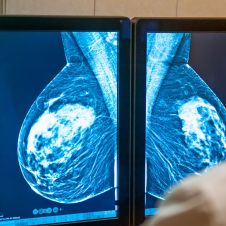

Proponen apoyos a cuidadores de enfermos de cáncer

La diputada Eleonor Martínez Gómez presentó una iniciativa para otorgar apoyos económicos y en especie a quienes cuidan y acompañan a pacientes con cáncer durante sus tratamientos, mediante reformas a la Ley de Salud del Estado de Morelos. La propuesta, presentada en sesión ordinaria, plantea adicionar una fracción al artículo 13...